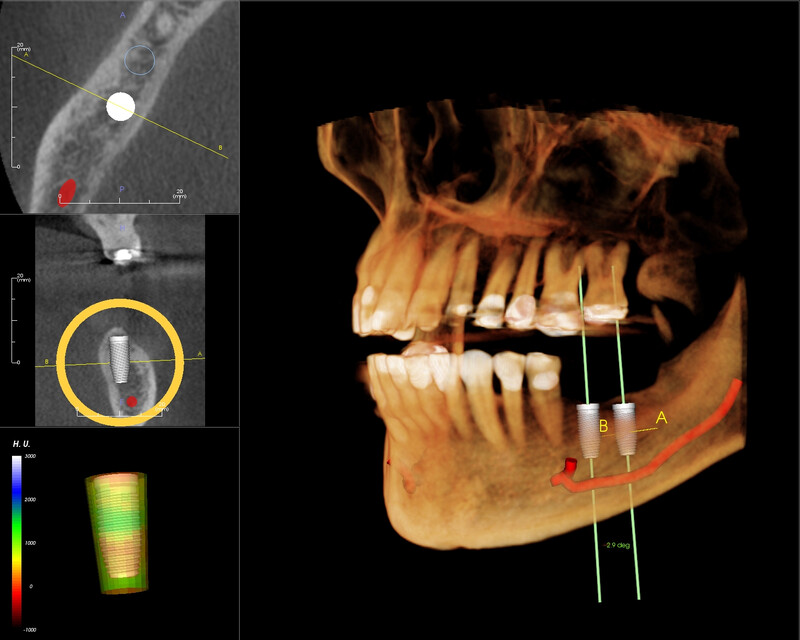

CBCT 3D kết hợp với phần mềm chuyên dụng cho phép bác sĩ:

- Mô phỏng vị trí đặt implant trước phẫu thuật

- Đo chính xác thể tích xương còn lại

- Xác định vị trí dây thần kinh và xoang hàm

- Đánh giá mối quan hệ giữa răng và các cấu trúc lân cận

CBCT 3D (Cone Beam Computed Tomography)

Ứng dụng: Cung cấp hình ảnh ba chiều với độ phân giải cao của xương hàm và các cấu trúc giải phẫu. Là tiêu chuẩn vàng cho lên kế hoạch cấy ghép implant, đánh giá răng khôn phức tạp và chẩn đoán bệnh lý xương hàm.

Ưu điểm: Hình ảnh 3D chi tiết, đo đạc chính xác, liều bức xạ thấp hơn CT Scanner.

Kết quả chẩn đoán hình ảnh được tích hợp trực tiếp vào hồ sơ bệnh án điện tử, giúp bác sĩ dễ dàng truy cập và so sánh trong quá trình điều trị. Hình ảnh CBCT 3D được sử dụng trực tiếp trong phần mềm lên kế hoạch implant kỹ thuật số, đảm bảo độ chính xác tối đa cho mỗi ca cấy ghép implant hay All-on-4.